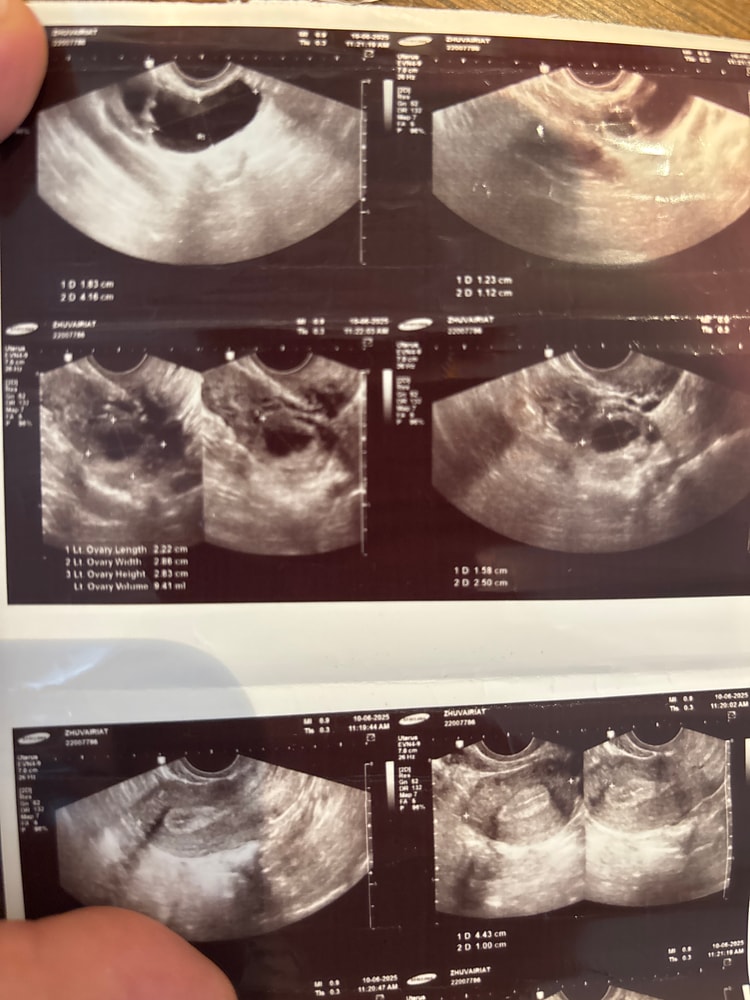

Изображение

Джамиля, ну похоже на жт, но мы же не узисты, поэтому не точно))🤷🏼‍♀️

Вы Же были у врача. Думаете мы тут лучше знаем. Если она не видит, то его нет. Возможно кистой переросло

Дюфастон с 16 по 25дц Укол ХГЧ 5000